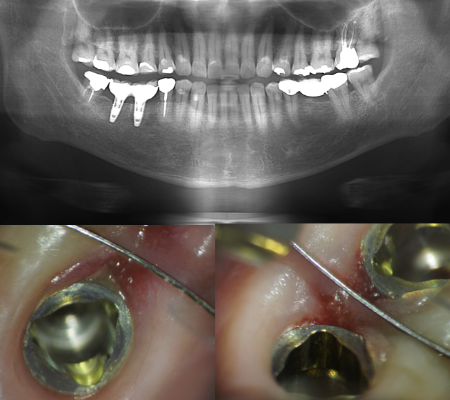

レントゲンとの併用

根管は完璧な清掃を行わなければ、「痛み」「腫れ」が進み、「根尖病巣」という非常に厄介で治りにくい病気にもなります。この病変をしっかり確認するため、根幹治療を行うに際し、レントゲンで根の構造を把握しますが、CT( 三次元立体画像) も利用します。

衛生士も顕微鏡拡大診療を

くぼ歯科では、衛生士にもマイクロスコープを使った診療をしていることで、

実際に歯肉の中を観察し、肉眼・触診ではなく歯石の有無を明確にすることができます。鏡で見せた患者様へのプラーク付着の説明より、マイクロスコープ(顕微鏡)での画像を録画し、画面上で拡大し、肉眼よりリアルなプラークの付着、歯石の付着を見ていただくことで、多くのメリットが生まれてくることでしょう。